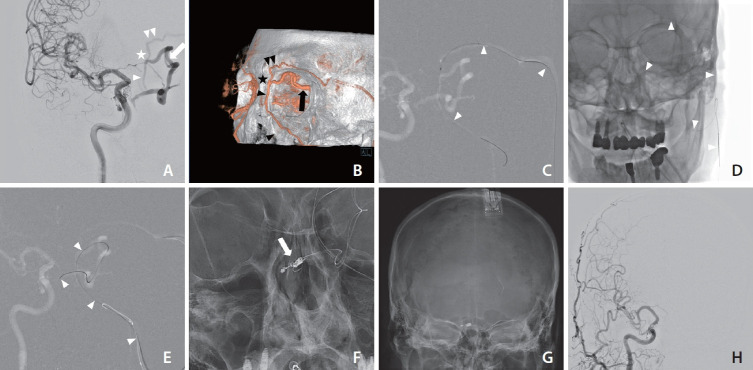

Management of cavernous sinus dural arteriovenous fistula (CSDAVF) continues to present significant challenges, particularly when the inferior petrosal sinus is thrombosed, collapsed, or angiographically invisible. In this study, we introduce facilitated retrograde access via the facial vein, which is employed in the transvenous embolization of CSDAVF with isolated superior ophthalmic venous drainage. We also present illustrative cases and technical points.